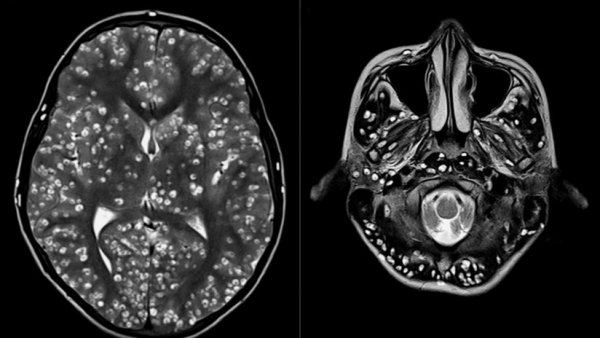

Tras practicarle una resonancia magnética y exámenes de ultrasonido, los especialistas encontraron que la corteza cerebral y el tronco encefálico del paciente estaban llenos de larvas.

El muchacho padecía neurocisticercosis, una enfermedad parasitaria originada cuando una persona ingiere huevos microscópicos de una tenia porcina y que afecta al tejido muscular. De ahí los parásitos se propagan al cerebro. Los personas infectadas pueden pasar mucho tiempo sin presentar síntomas.